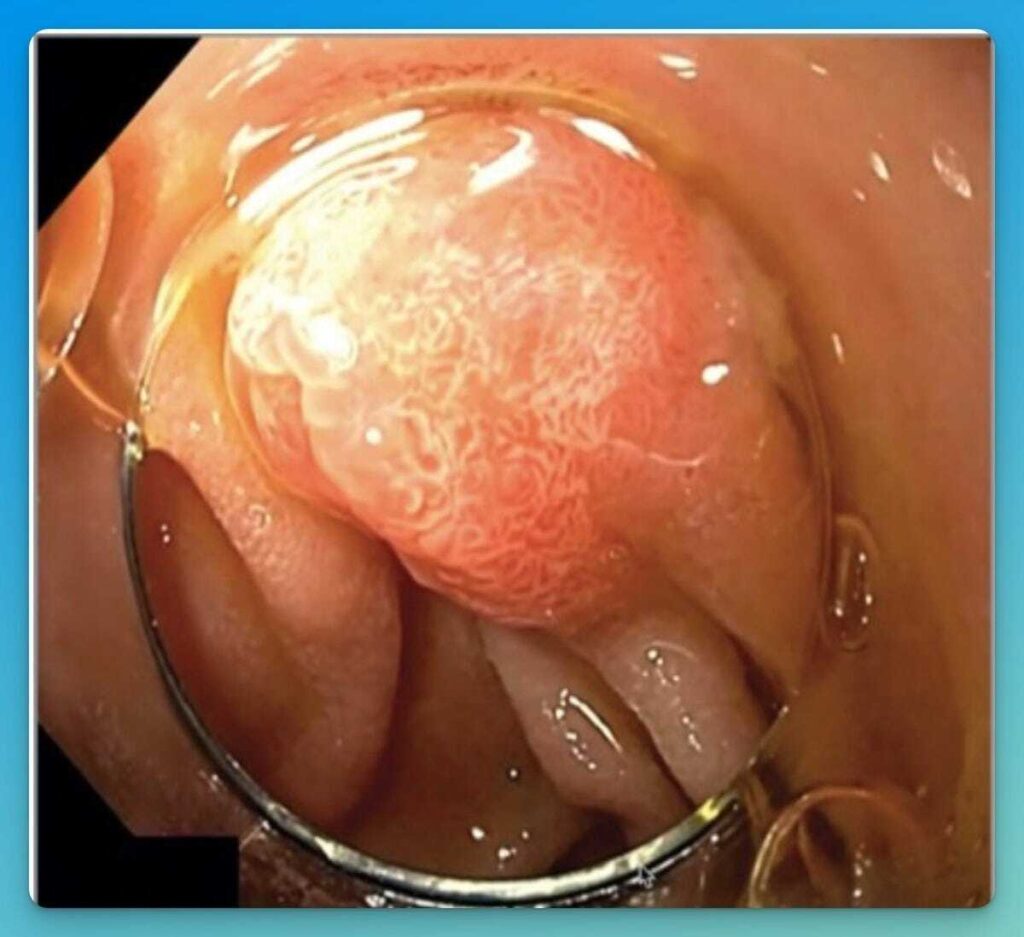

Inflammatory Fibroid Polyps (IFP) or Vanek Tumors of the GI Tract

The images show Vanek tumors of the duodenum (left) and the stomach (right) (Stomach photo by @patholwaker) Inflammatory fibroid polyps (IFP) or “Vanek tumors” are rare submucosal lesions arising from a reactive, benign granuloma-like process of the GI tract (1). This tumor is most commonly located in the stomach (70%), ileum (29%) and colon (6%) (2-4). […]